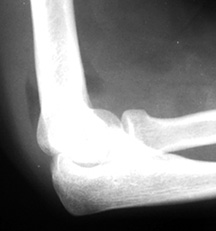

X-ray demonstrating positive fat pad sign.

Is There Joint Effusion?

The way to evaluate joint effusion in the elbow is to look for a positive fat pad sign. Normally, when the elbow is flexed to 90°, the anterior fat pad may be seen just anterior to the joint; the posterior fat pad is not seen because it is located in the intercondylar fossa. With joint distention, the fat pads are displaced away from the joint in the anterior aspect; the fat pad will be elevated away from the joint and the posterior fat pad will be visible.

If a positive fat pad sign is not present in a child, significant intra-articular injury is considered unlikely; but on the other hand, if a visible fat pad sign is demonstrated without the appearance of a fracture, the patient should be treated as having a non-displaced fracture and should be splinted for two weeks and then re-evaluated. It is generally agreed that in the case of trauma, a displaced posterior fat pad is virtually pathognomonic of the presence of a fracture.